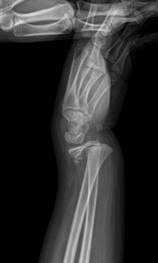

엑스레이(X-ray): 성장판 손상의 유무와 정도를 확인하기 위해 X-ray 촬영을 시행합니다. 그러나 일부 경우 성장판 손상은 엑스레이에서 명확하게 보이지 않을 수 있습니다.

MRI: X-ray로 확인되지 않는 성장판 손상의 경우 MRI를 통해 연골과 연부 조직 상태를 자세히 확인합니다. 특히 성장판 부위의 상태를 더 정밀하게 볼 수 있습니다.

CT 스캔: 뼈 구조와 손상의 위치를 더 자세히 파악하기 위해 CT 스캔이 사용될 수 있습니다.